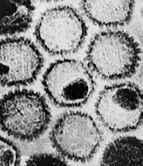

• Обложка: Креативный лимфоузел